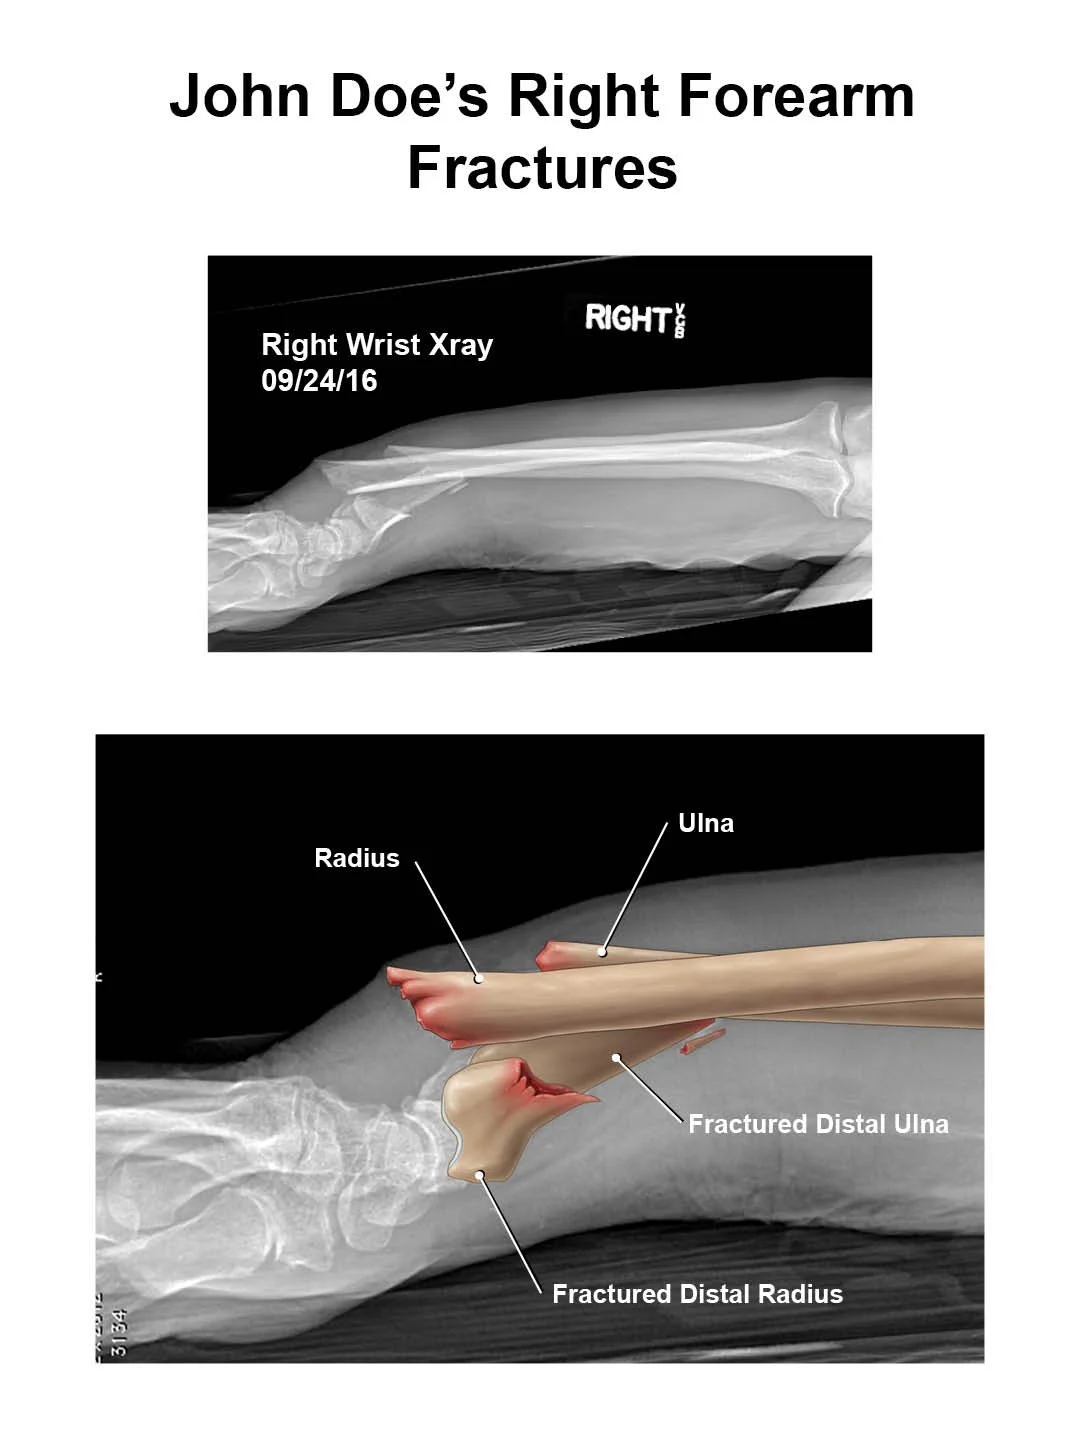

This illustration is a mock medical legal exhibit for a plaintiff who has suffered a broken wrist. The aim of the exhibit is to clearly connect the illustration to the radiology and to make the complex anatomy more understandable for lay audiences serving in the jury.